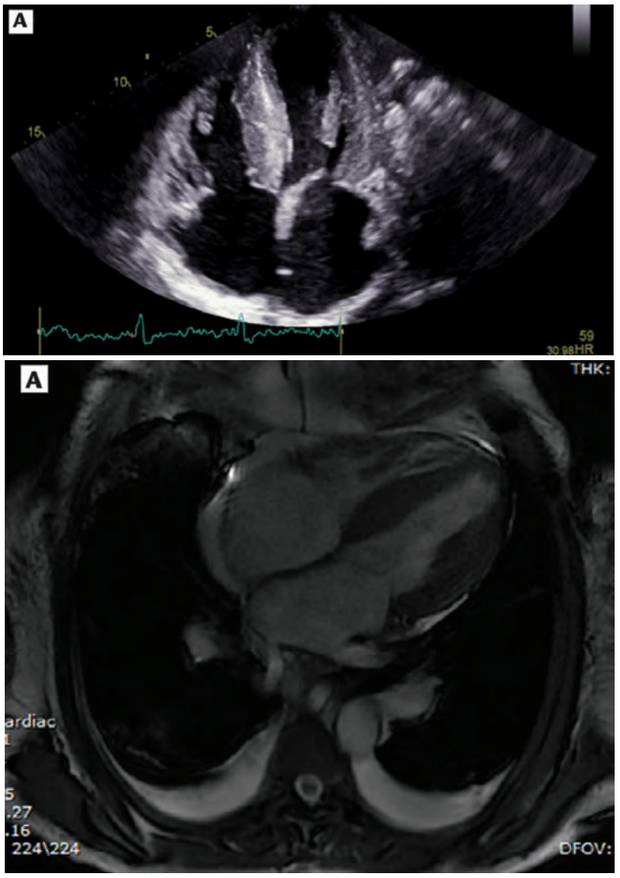

Acometimento cardíaco pela amiloidose, mostrando espessamento da parede cardíaca e redução nas cavidades no esocardiograma (acima) e ressonância (abaixo) – fonte